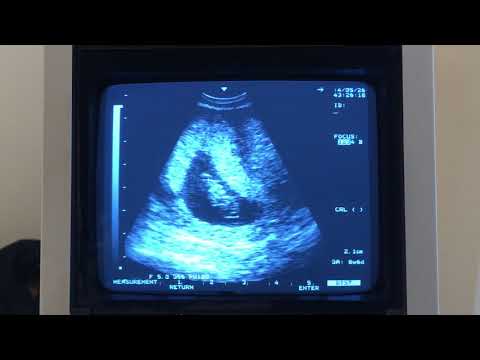

คุณหมออัลตร้าซาวด์ให้ด้วยค่ะ

ดูเป็นรูปเป็นร่างขึ้นมาแล้ว ^_^